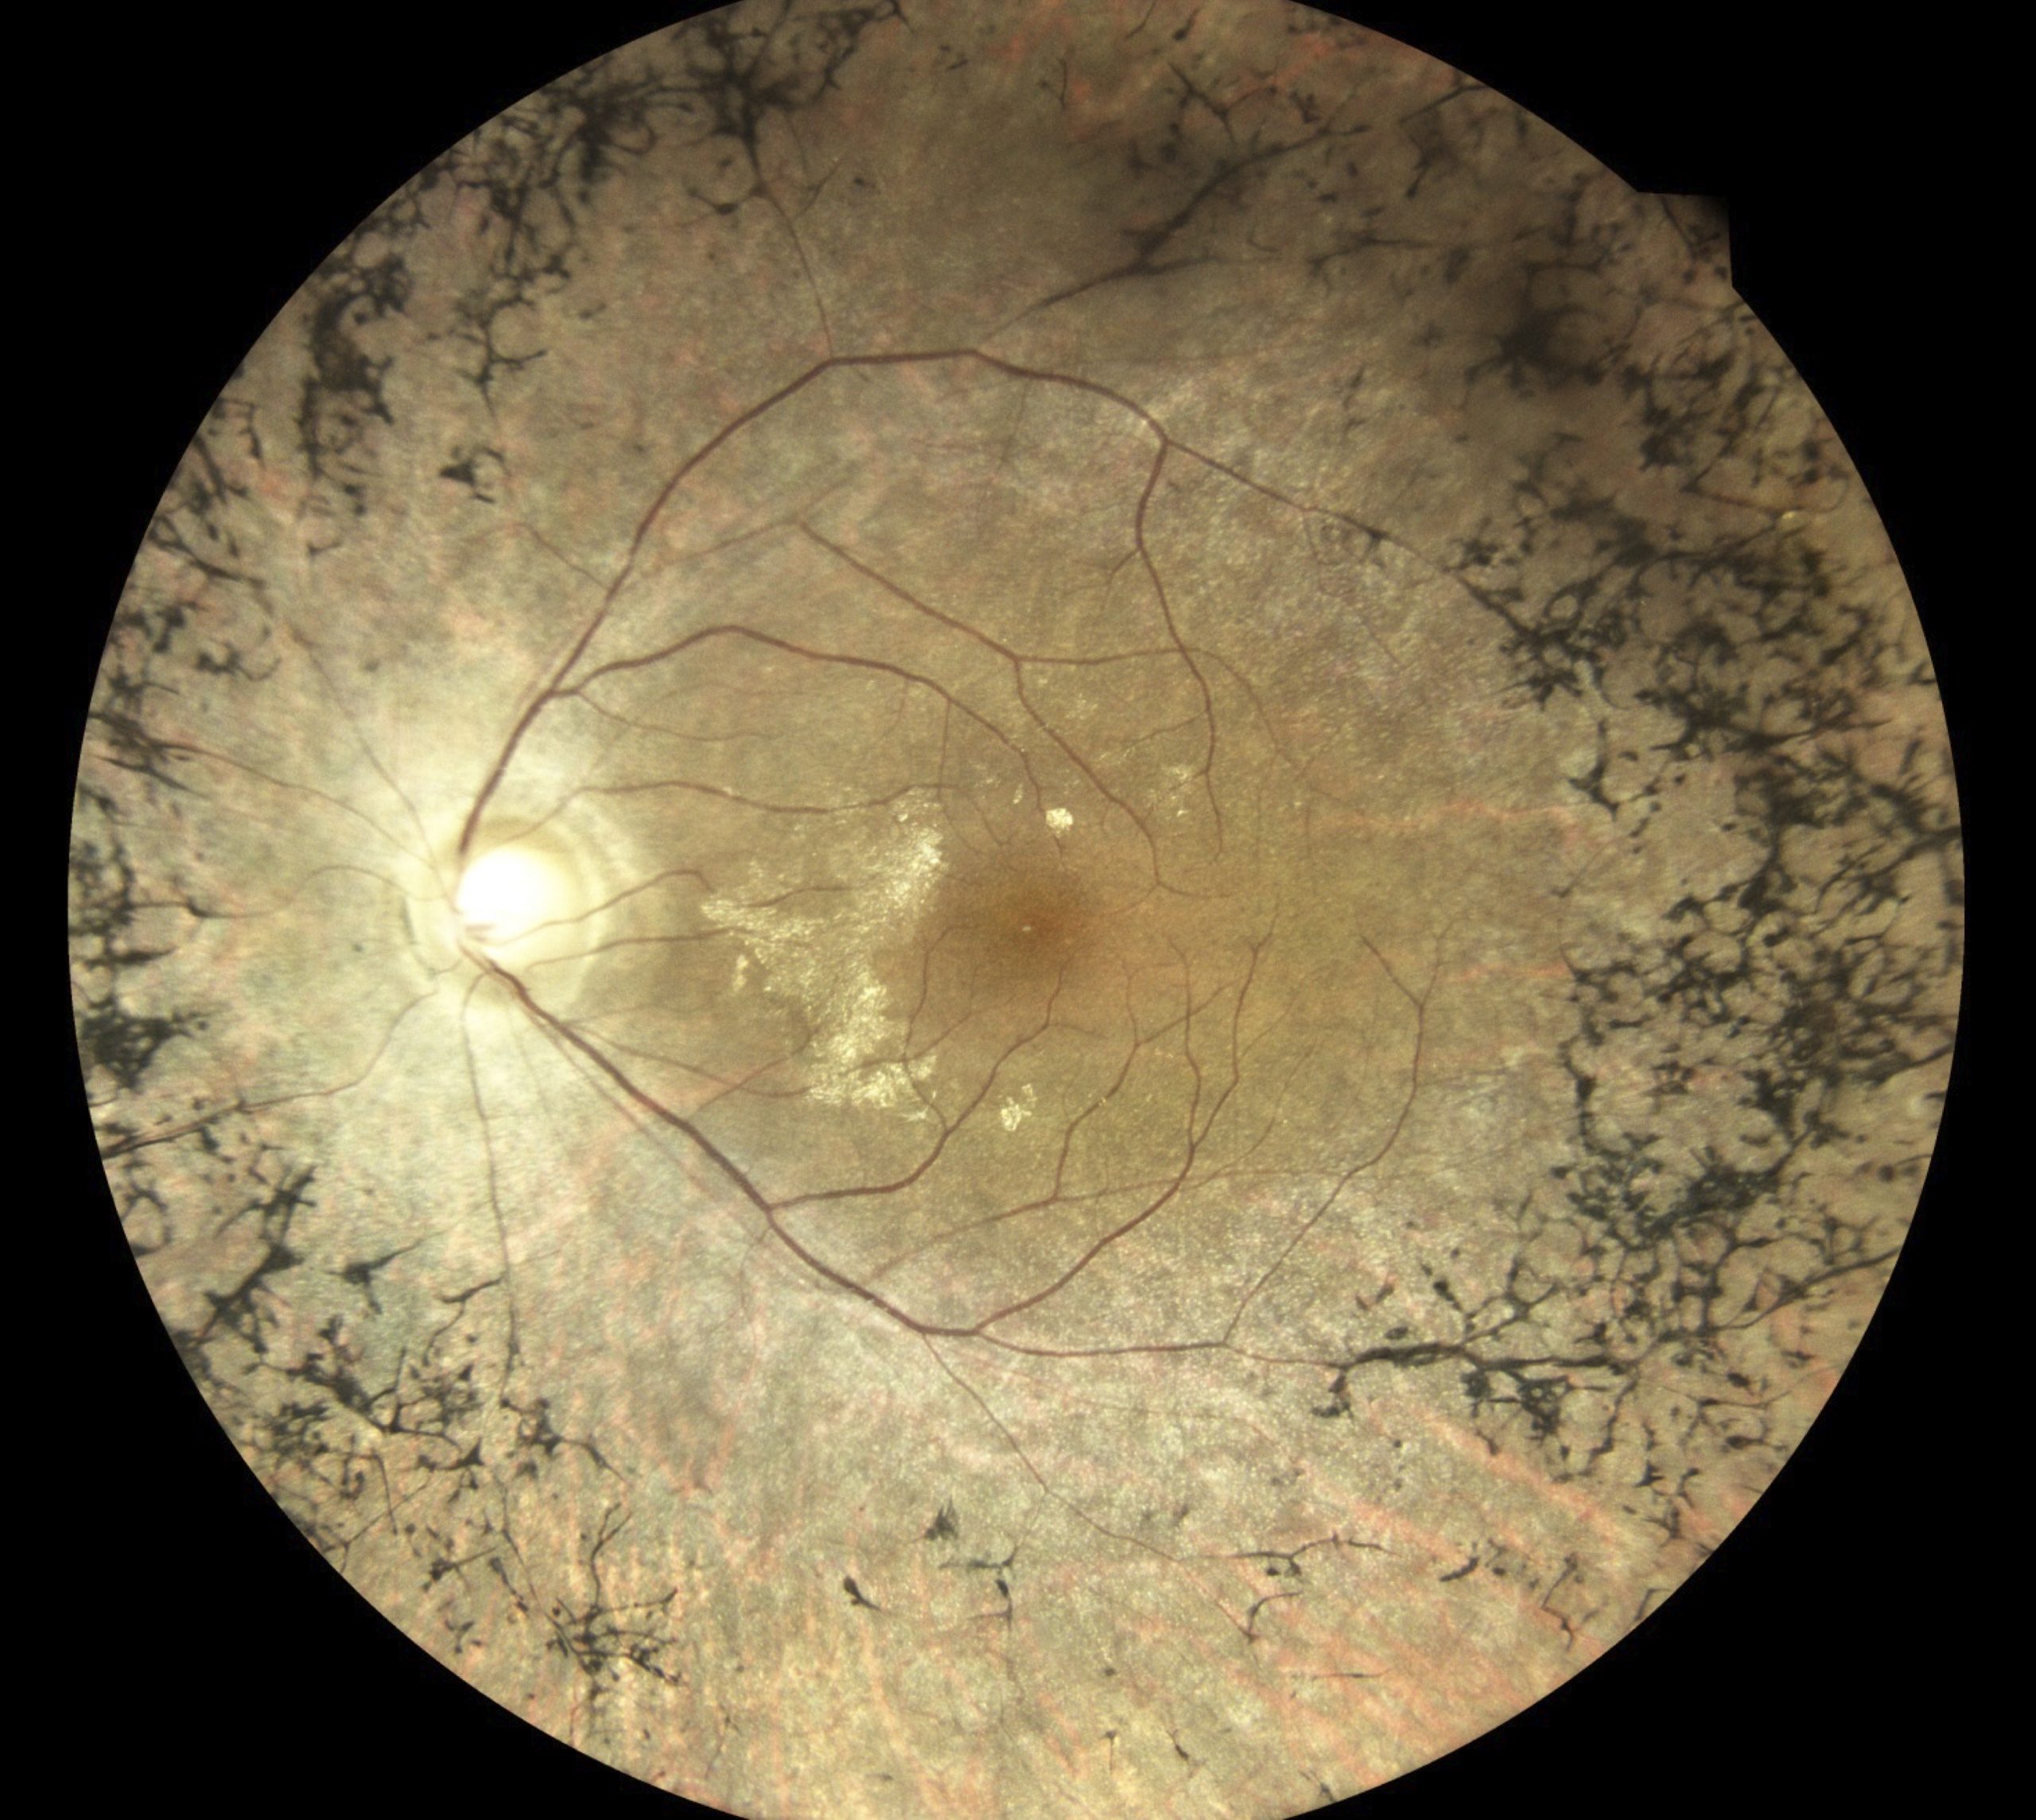

Abbildung 1: Dies ist das Foto der Netzhaut eines an Choroideremie erkrankten Patienten. Man erkennt den Sehnerv und die von ihm ausgehenden Blutgefäße. Im Zentrum ist eine Restinsel mit weitestgehend intakter Netzhaut zu erkennen. Die weiter zum Rand hin gelegene Netzhaut ist vollständig verkümmert (atrophiert), sodass man die Blutgefäße der Aderhaut (Choroidea) erkennt.